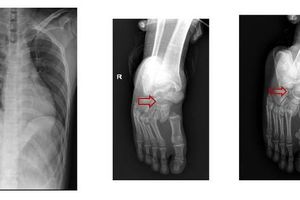

Thang máy rơi từ tầng 7 khiến 2 nam thanh niên ngã chấn thương cột sống. Dù được cứu chữa kịp thời nhưng cả 2 bị liệt hoàn toàn 2 chân

Mới đây, Bệnh viện Nhân dân 115 (TP HCM) đã tiếp nhận 2 trường hợp làm nghề sửa thang máy bị rơi thang khi đang sửa chữa khiến chấn thương cột sống. Cả 2 trường hợp đã được các bác sĩ kịp thời cứu chữa bảo vệ tính mạng. Tuy nhiên, do tình trạng chấn thương nặng khiến cả 2 bị liệt 2 chân.2 bệnh nhân nam nhập viện trong tình trạng đau đớn, liệt hoàn toàn 2 chân, bí tiểu… Khai thác bệnh sử, trong lúc nam bệnh nhân 28 tuổi, quê ở Hải Dương, đang sửa cáp thang máy thì người đồng nghiệp (26 tuổi, quê Tiền Giang) bước vào thang khiến thang quá tải rơi xuống từ lầu 7.

Sau khi nhập viện, cả hai được phẫu thuật khẩn nắn chỉnh cột sống, giải ép tủy… Sau mổ, cả hai tiếp tục được tập phục hồi chức năng với các dụng cụ như di chuyển xe lăn, nạng, nẹp… để có thể thực hiện được các hoạt động sống hàng ngày một cách độc lập nhất.Các bác sĩ cũng khuyến cáo người bệnh phải kiên trì vận động nhằm ngăn ngừa biến chứng và thương tật thứ cấp đối với người bị tổn thương tủy sống như loét da do đè ép, nhiễm khuẩn hô hấp, nhiễm trùng tiết niệu, huyết khối tĩnh mạch sâu, teo cơ, cứng khớp, co rút biến dạng... Chương trình tập bao gồm cả tập thở, tập ho, tập vận động đúng tư thế, tập theo tầm vận động, tập di chuyển tại giường, tập di chuyển từ giường ra xe lăn và ngược lại,...